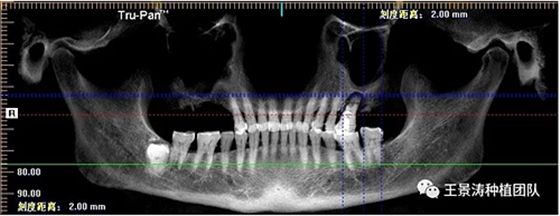

下述病例則是15區(qū)域的即刻種植,15因牙冠折斷于齦下,無法樁核冠修復(fù),則考慮種植修復(fù)。但拍攝CBCT后發(fā)現(xiàn)根尖距上頜竇底距離較短。患者為年輕女性,無全身系統(tǒng)疾病且可利用上頜竇底與根尖皮質(zhì)骨雙側(cè)皮質(zhì)骨固位,且此位置可通過頰側(cè)軟組織減張技術(shù)獲得嚴(yán)密封閉牙槽窩。因其根尖距上頜竇距離較低,遂拔除15后行上頜竇內(nèi)提升,埋入式種植,最終修復(fù)的完成。

左側(cè)下頜第二磨牙及右側(cè)下頜第一磨牙同時(shí)即刻種植病例?;颊吣贻p女性,無系統(tǒng)性疾病。37及46殘冠及殘根,且46劈裂,無法冠修復(fù),必須拔除。37根尖慢性炎癥,大量肉芽組織存在,46根分叉較高,根分叉骨質(zhì)尚可。CBCT示:根尖骨質(zhì)至下牙槽神經(jīng)管距離可滿足種植體的初期穩(wěn)定性,遂考慮即刻種植,并在種植體周邊填入骨粉并覆蓋骨膜,雙側(cè)的種植體初期穩(wěn)定性相差無幾,但考慮到37根尖慢性炎癥較大,遂給予埋入式種植。